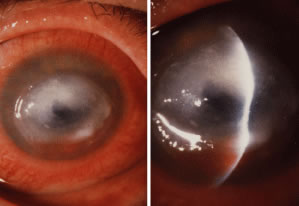

Candida infection typically produces epithelial ulceration, focal necrotizing stromal inflammation, moderate cellular infiltrate and edema in the adjacent stroma, and mild or moderate iritis in the early stages, indistinguishable from bacterial keratitis (Figs. 15, 16, and 17). Fungal elements cannot be detected by biomicroscopy. If untreated, the keratitis evolves to produce dense suppuration and necrosis of the deep stroma. Although multifocal suppuration may develop in polymicrobial keratitis, there is no distinctive sign of mixed Candida and bacterial infection (Fig. 18).

Advanced, severe filamentous fungal or yeast keratitis is indistinguishable from keratitis caused by virulent bacteria such as Staphylococcus aureus or Pseudomonas aeruginosa. The area of epithelial and stromal ulceration is large. Dense, opaque, homogenous, yellow-white stromal necrosis develop and is surrounded by confluent cellular infiltrate and full-thickness stromal edema (Figs. 19, 20, 21). Hyphal elements may penetrate Descemet's membrane and endothelium and be visualized in the anterior chamber. Fibrinous material accumulates over the endothelium, anterior chamber angle, and iris. Pain is typically severe. Secondary ocular hypertension may ensue. Progressive stromal necrosis leads to corneal perforation and, rarely, consecutive endophthalmitis.